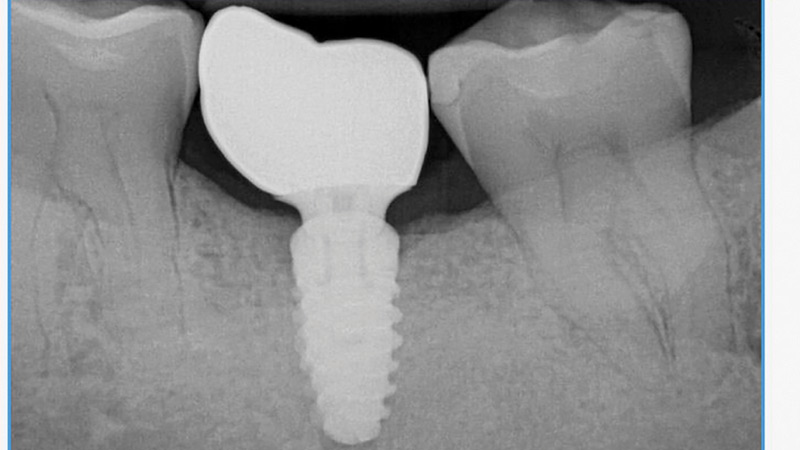

Risk Factors In Implant Dentistry: Unrestorable Implants

Arlin-7b2 alternate text for this image

This article is the fifth in a series by the author submitted to and published in Oral Health. The previous four articles of the series were published in the August 2015 to 2018 issues with the titles: Surgical Risk Factors in Implant Dentistry: Influence on Failures and Bone Loss1, Patient Related Systemic Risk Factors2, Patient … Read more